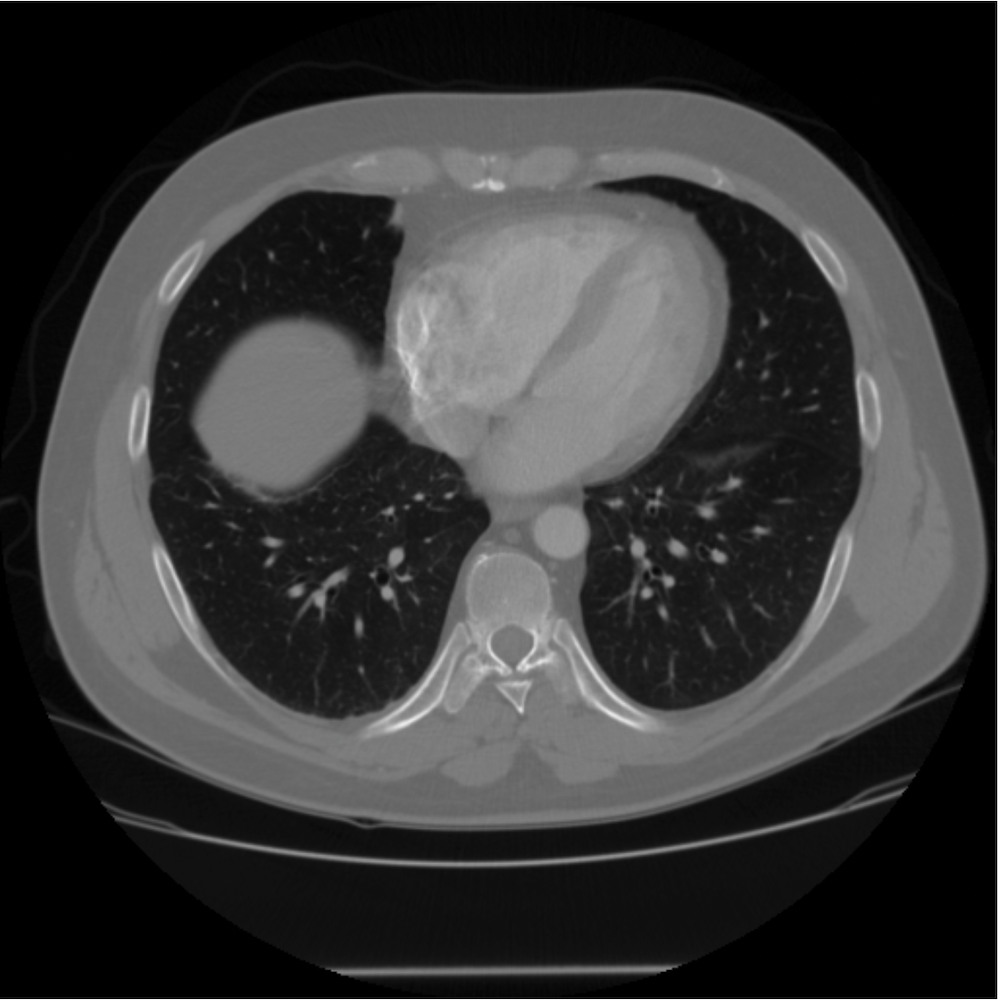

Lung Data.

The LIDC/IDRI dataset (Armato III et al., 2011) is designed specifically for training and comparing deep learning-based methods for low-dose CT reconstruction, and consists of helical thoracic CT scans. We chose 40,000 CT scan slices from LIDC/IDRI , data from approximately 800 patients, to define the dataset used in this paper. We use the same 40,000 examples chosen by Leuschner et al. (2019).

Due to computational constraints, we worked with two image sizes namely, and pixels. To produce smaller images we used cropping and rescaling of the slices of the reconstructed 3D objects in the datasets. For images, we took crops from the chip and composite material slices, and then rescaled them to size using bilinear interpolation. For the Lung dataset, we rescaled directly each of the slices in the dataset to . For the images, we simply took crops of size from the CT reconstruction datasets described above. All these crops are independent with no overlap. The final images are then split into disjoint train and test datasets.